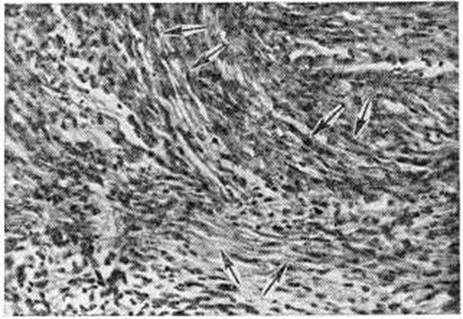

Макроскопически Спонгиобластома полярная имеет вид хорошо отграниченного узла белого или бело-серого цвета плотной консистенции (рисунок 1), часто с кистами, реже с очагами кровоизлияний на разрезе. Микроскопически Спонгиобластома полярная состоит из веретенообразных вытянутых клеток (спонгиобластов) с овальными или круглыми светлыми ядрами, содержащими большое количество хроматина. Клетки располагаются параллельно, формируют пучки различной толщины, переплетающиеся в различных направлениях (рисунок 2). Митозы немногочисленны. Для Спонгиобластома полярная характерны гидропическая и слизистая дистрофия клеток с вакуолизацией цитоплазмы. Кровеносных сосудов в опухоли немного, пролиферация эндотелия не наблюдается.